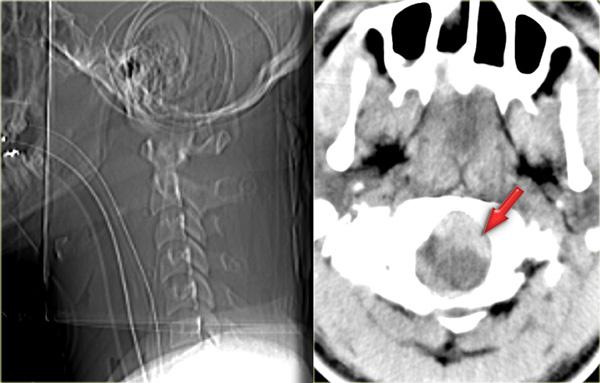

Hình bên trái là hình ảnh của một hành khách 26 tuổi không thắt dây an toàn trong vụ tai nạn giao thông, bị văng ra khỏi xe.

Bệnh nhân có nhiều tổn thương bao gồm tụ máu dưới màng cứng, tràn máu màng phổi, chảy máu ngoài màng cứng tủy sống, gãy cột sống ngực, gãy mỏm ngang L3 trái và gãy xương đòn trái.

Không có thiếu hụt thần kinh khi khám thực thể.

Hãy nghiên cứu các hình ảnh trước, sau đó tiếp tục đọc.

Các phát hiện bao gồm:

- Gãy qua nền mỏm răng

- Phù nề phần mềm trước cột sống

- Đứt dây chằng gian gai C1-C2

- Không quan sát được cột sống cổ thấp

Xem các hình ảnh CT và sau đó tiếp tục đọc.

CT xác nhận các phát hiện trên X-quang và cho thấy thêm hai phát hiện bổ sung:

- Hình ảnh qua phần bên của C2 cho thấy rõ ràng đường gãy đi qua thân C2, tức là gãy mỏm răng loại III.

-

Màng cứng phía sau ở vị trí bình thường, nhưng màng cứng phía trước bị di lệch (mũi tên).